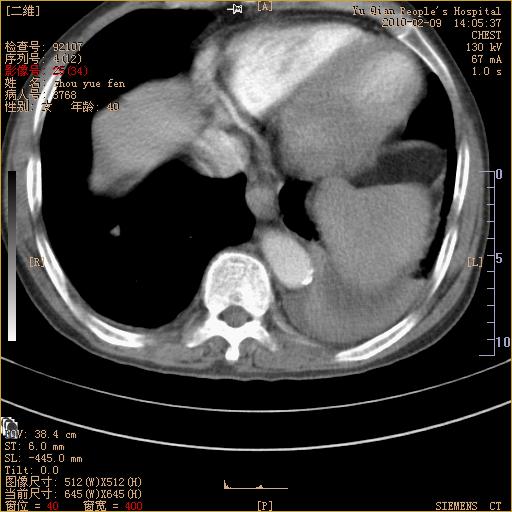

男性,73岁,咳嗽咳血数天,诊为肺ca伴左肺下叶后段阻塞性炎症、肺不张妥否?

右下肺有转移?

左下肺中央型肺癌伴结段形肺不张,左侧胸腔积液,纵隔内见部分增大淋巴结(反应性增生或转移)

左下基底干支气管明显变窄。

左肺下叶基底段支气管狭窄,左肺门增大,左肺下叶团片状病灶。中心型肺癌伴柱塞性炎症可能大,建议支气管镜检查。

左下肺中央型肺癌伴节段性肺不张,左侧胸腔积液,纵隔内见肿大淋巴结

左下基底段支气管变窄。建议进一步纤支镜检查。

1、左肺下叶后基地段肺癌伴阻塞性炎症,左下肺门淋巴结转移。2、左侧胸腔积液。